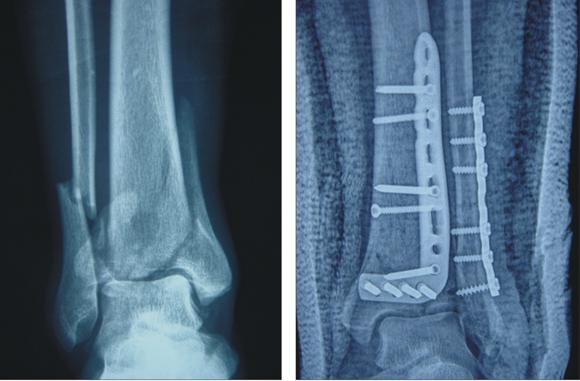

我们小腿的胫骨下端有一种典型的骨折,叫pilon骨折。常常发生在车祸,高处坠落,剧烈运动当中。这种骨折最大的特点就是破坏了踝关节的结构完整。那么,对于这种典型的骨折我们术后该如何康复呢?那就跟着康复师学起来吧。

这种手术往往需要进行手术内固定,使用钢板,螺钉等等。因为是粉碎性骨折,所以,即使做了内固定,术后为了安全起见,还会在用石膏,夹板或者支具再辅助固定2~3周。